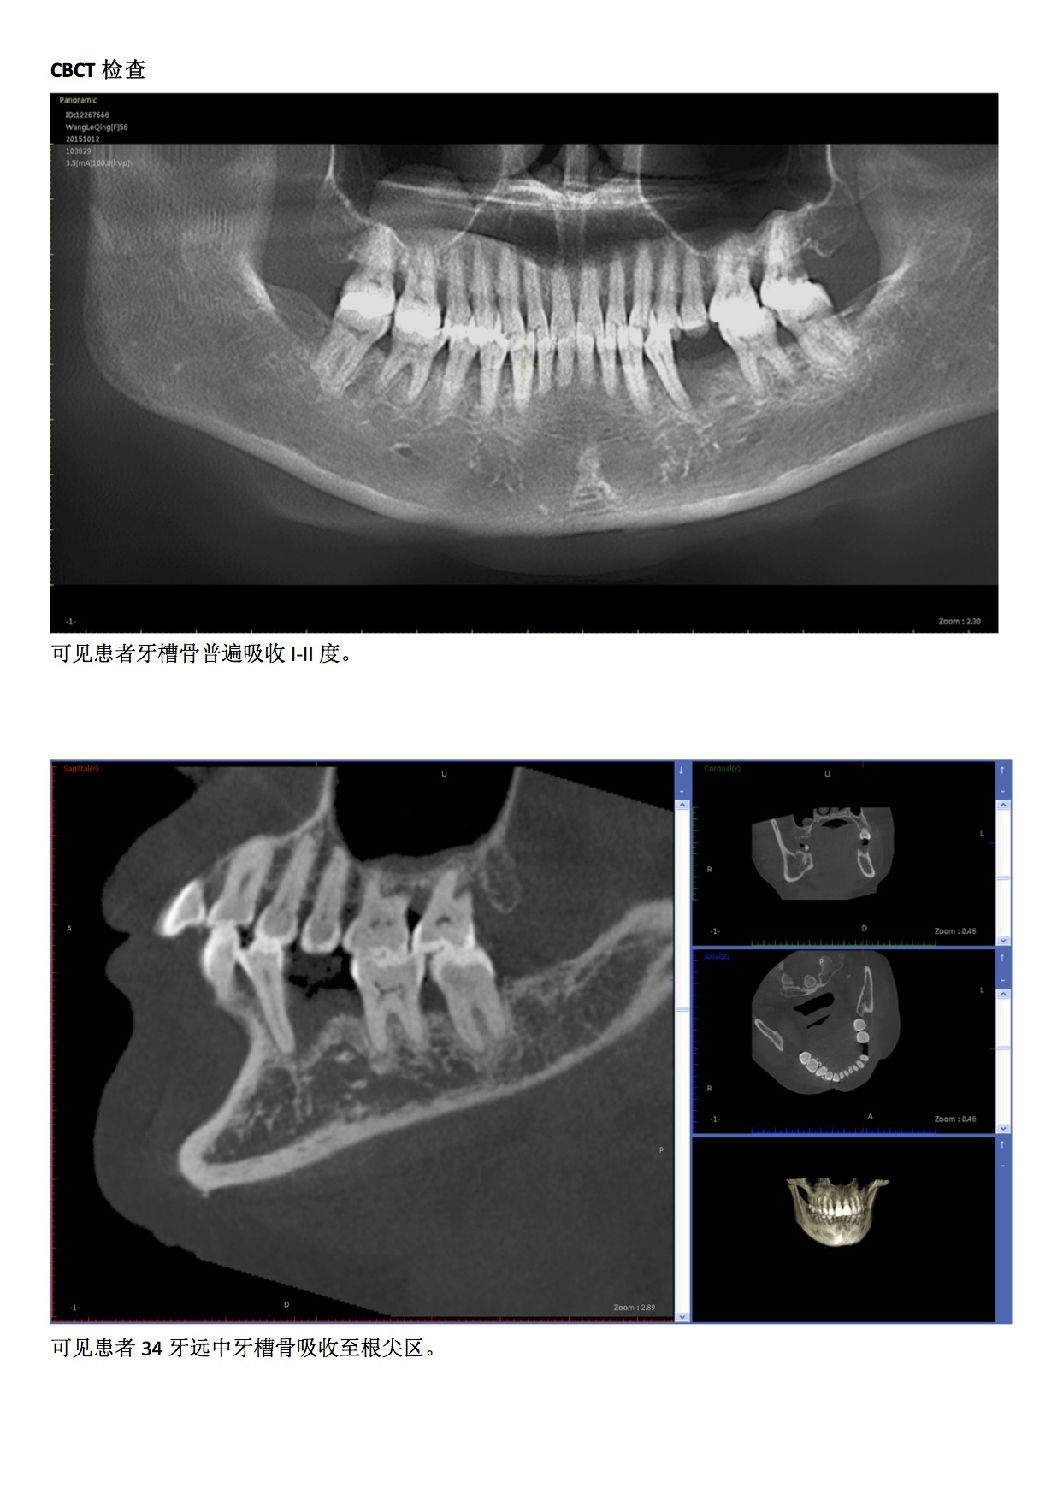

牙周病患者種植治療+鄰牙GTR病例匯報